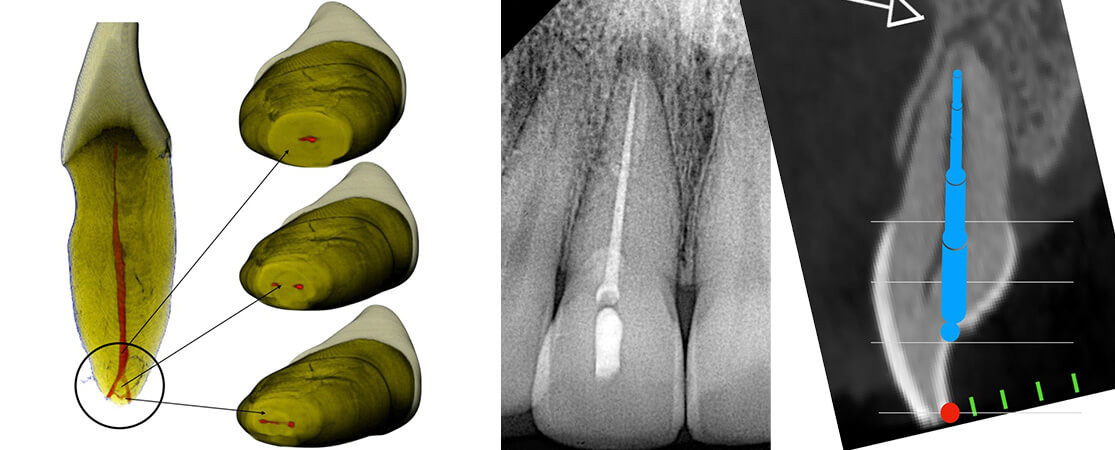

Totally or partially calcified canals present a constant challenge in clinical endodontics. Negotiating obliterated canals could be from difficult to nearly impossible. The risk of procedural accidents, such as perforation and instrument separation, is high. However, under the magnification provided by a dental operating microscope the whole procedure of dealing with obliterated canals could become very predictable. Complete root canal space obliteration associated with apical periodontitis is relatively rare. This lecture is designed to help the clinician deal predictably with challenging cases of partial or diffuse calcification in Endodontics and blocked canals.

3. Describe a new free hand technique with specially designed files to penetrate through calcified canals (The BRAT technique)